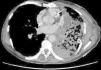

Pulmonary vein obstruction is usually an early complication, occurring during the first few hours after transplantation, and causes severe symptoms. Marked hypoxia, pulmonary edema, and pulmonary infiltrates are observed. If the lower lobe is more severely affected, a high suspicion for such a complication is warranted, and an early additional diagnostic test should be ordered. The initial test should be a transthoracic or transesophageal echocardiogram, in spite of this test being only useful for diagnosis when performed by an experienced operator, due to a challenging visualization and interpretation after recent surgery 6. Alternatively, chest CT angiography can be used, which also allows artery suture and distal vascularization to be assessed and reconstructions to be produced. CT angiography establishes the diagnosis in most cases. Anticoagulation using heparin and clinical course monitoring is used to manage partial thromboses and stenoses. In the event of a complete vein obstruction or a poor course, in patients with a very recent surgery, re-transplantation or lobectomy for double-lung transplantations, may be needed. If the patient is in a stable condition, several days have elapsed, and anatomic characteristics are favorable, an angioplasty with dilation and stent implant can be considered.

Figure 4. CT image showing extensive lung infiltrates in lower left lobe resulting from lower pulmonary vein obstruction.